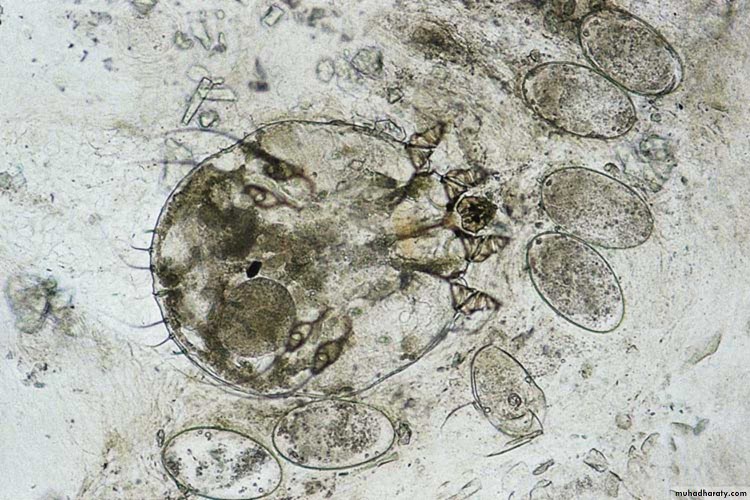

Яйца Cheyletiella под микроскопом